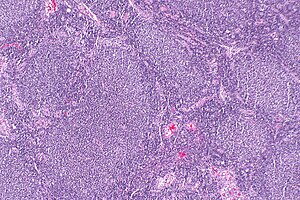

| Micrograph of a follicular lymphoma, showing the characteristically abnormal lymphoid follicles that gave the condition its name. H&E stain. | |

Follicular lymphoma (FL) is a cancer that involves certain types of white blood cells known as lymphocytes. The cancer originates from the uncontrolled division of specific types of B-cells known as centrocytes and centroblasts. These cells normally occupy the follicles (nodular swirls of various types of lymphocytes) in the germinal centers of lymphoid tissues such as lymph nodes. The cancerous cells in FL typically form follicular or follicle-like structures (see adjacent Figure) in the tissues they invade. These structures are usually the dominant histological feature of this cancer.[1]

The diagnosis of FL depends on examining involved tissues for histological, immunological, and chromosomal abnormalities that are indicative of the disease. FL usually involves enlarged lymph nodes populated by abnormal follicles (see adjacent picture) that when examined histologically contain a mixture of centrocytes or centroblast surrounded by non-malignant cells, mostly T-cells. The centrocytes, which typically outnumber centroblasts, are small to medium-sized B-cell lymphocytes that characteristically exhibit cleaved nuclei; the centropblasts are larger B-cell lymphocytes without cleaved nuclei.[11] Rare cases of FL may show lesions that contain tissue infiltrations dominated by B-cells with features of precursor (i.e. "blast") cells, monocytes, or malignant mantle cells such as those found in mantle cell lymphoma.[1] Immunochemical analyses reveal that these cells generally express B-cell surface markers including the CD10 (60% of cases), CD20, CD19, CD22, and CD79 but not CD5, CD11c, or CD23 cell surface proteins;[4] genomic analyses reveal that these cells contain t(14:18)(q32:q21.3) translocation (85-90% of cases), 1p36 deletions (60-70% of cases), and with far less frequency the other genomic abnormalities listed in the above sections on Pathophysiology and Presentation and course. None of these protein markers or genomic abnormalities are diagnostic for FL, e.g. the t(14:18)(q32:q21.3) translocation is found in 30% of diffuse large B-cell lymphoma and in a small number of reactive benign lymph nodes. Rather, the diagnosis is made by a combination of histological, immunological, and genomic abnormalities.[4] According to World Health Organization (WHO) criteria, differences in the microscopically determined morphology of these tissues can be used to diagnose and categorized FL into the following 3 Grades with grade 3 having A and B subtypes:[51]